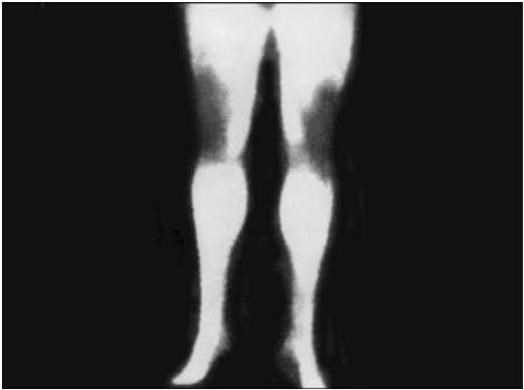

Рис. 3 в. Термограмма нормальных коленных суставов. Их контуры ровные, симметричные, со сниженным теплоизлучением